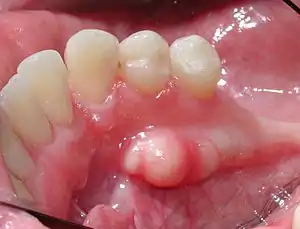

Mandibular torus in premolar area

Torus mandibularis is a bony growth in the mandible along the surface nearest to the tongue. Mandibular tori usually are present near the premolars and above the location on the mandible of the mylohyoid muscle attachment.[1] In 90% of cases, a torus is on both inner sides of the mandible (left and right); however, they may differ in size.